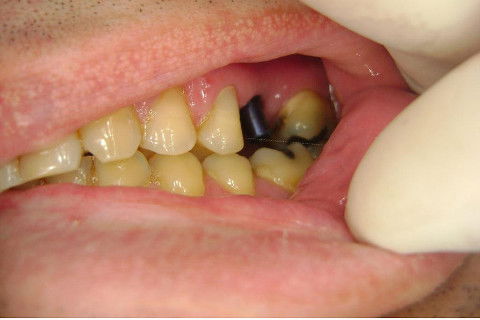

Instalação de um implante em região do 26. Utilizamos um implante cone morse Alvim Neodent 4.3 X 11,5. Foi uma cirurgia muito rápída e minimamente traumática, sem retalho e sutura.

Fotos do caso